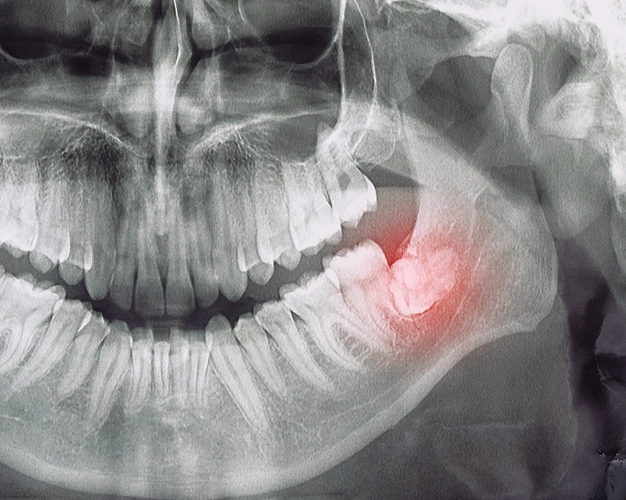

Wisdom teeth don’t always have to be removed. In fact, if you have the space for them and they come in correctly, they can be beneficial. However, if you don’t have the space in your jaw to accommodate the teeth, they can cause damage to your surrounding teeth, be painful, or become impacted, that is, stuck beneath the gums.

- Impaction